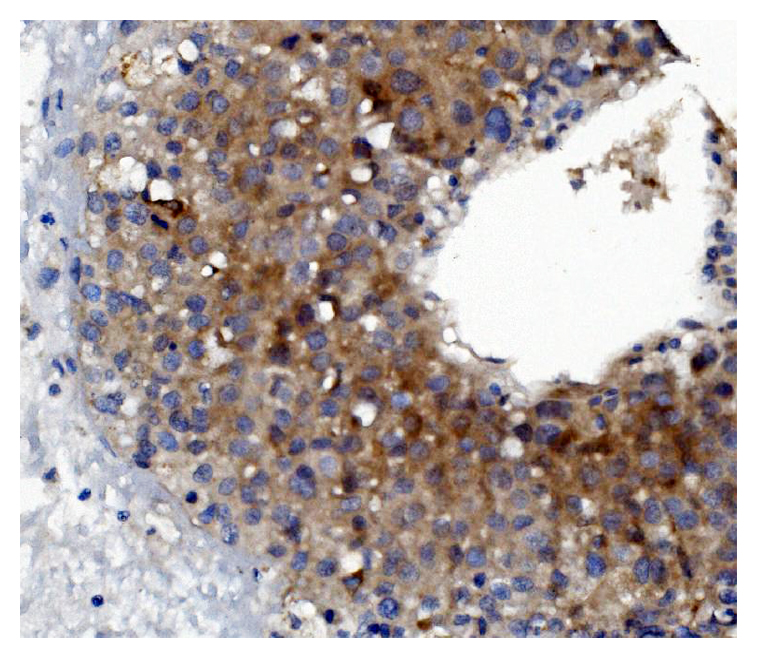

IHC analysis of GSDMD using anti-GSDMD antibody (M02842-1).

GSDMD was detected in a paraffin-embedded section of human lymph gland tissue. Biotinylated goat anti-mouse IgG was used as secondary antibody. The tissue section was incubated with mouse anti-GSDMD Antibody (M02842-1) at a dilution of 1:200 and developed using Strepavidin-Biotin-Complex (SABC) (Catalog # SA1021) with DAB (Catalog # AR1027) as the chromogen.